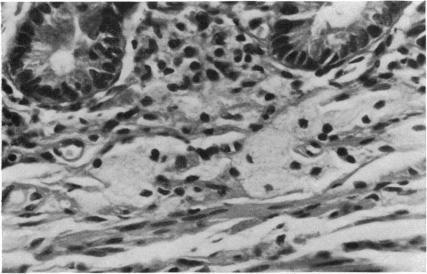

Two cases of Whipple's disease are reported in which a parallel course is confirmed between the clinical and ultrastructural findings. This is not so with light microscopy since it takes much longer for these findings to return to normal. In case 1, the presence of bacilli circulating freely in the sinusoid of a lymph node is described. Case 2 demonstrates the existence of special granulomata formed by atypical macrophage histiocytes which appear in coagulative necrosis together with a closely adherent crown of lymphocytes. Furthermore, these histiocytes have moved towards the deepest part of the lamina propria, and have become dissociated from the muscularis mucosae causing a diverticulosis of the small intestine.

报告了两例惠普尔病,其临床和超微结构检查结果呈现平行关系。而光学显微镜检查则不然,因为这些结果恢复正常所需时间长得多。病例1描述了杆菌在淋巴结窦中自由循环的情况。病例2显示了由非典型巨噬细胞组织细胞形成的特殊肉芽肿的存在,这些细胞与紧密附着的淋巴细胞冠一起出现在凝固性坏死中。此外,这些组织细胞已向固有层最深部移动,并与黏膜肌层分离,导致小肠憩室形成。